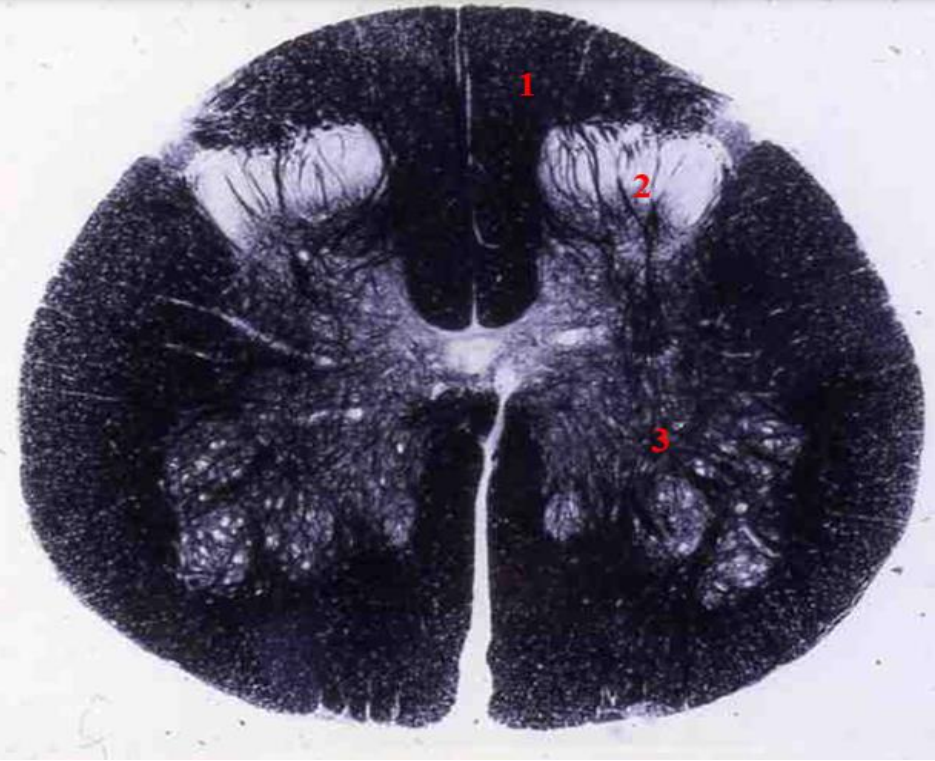

cervical cord

- fibre tracts are larger

- grey matter is large

- brachial plexus

- no lateral horn

fasiculus gracilis

fasciculus cuneatus

posterior horn

anterior horn